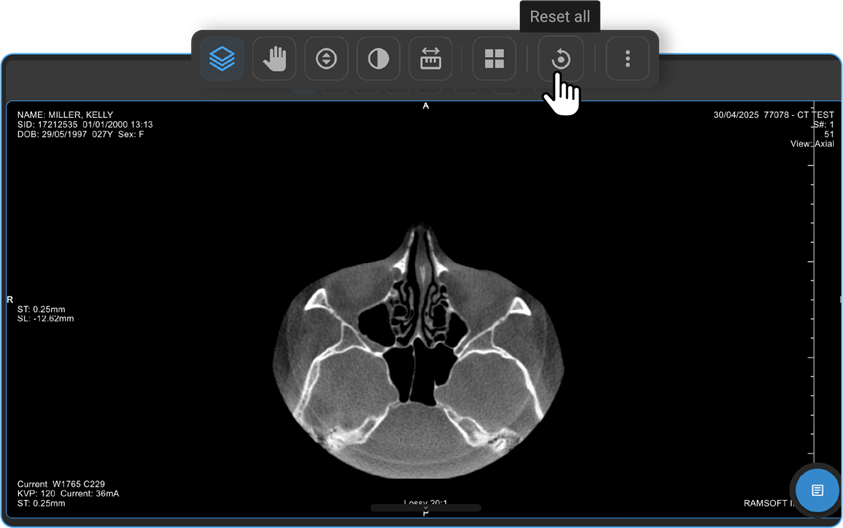

How Do I Reset All Changes?

• The Reset All option appears on the toolbar only if you’ve applied changes.

• Click it to revert everything to default.

• Once reset, the option disappears.